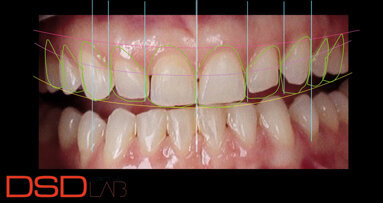

Přesné naprogramování a vosková modelace okluze se sekvenčním vedením s dominancí špičáků vyžaduje velké odborné znalosti. Účelem tohoto článku je ukázat způsob našeho využití digitálních postupů při diagnostice vycházejících z CAD programování okluze a výroby protetických konstrukcí pomocí CAM – to vše s cílem zjednodušit mana­gement složitých výrobních procesů. Tyto postupy vedou k větší individualizaci designu okluze u nově vznikající skupiny pacientů s narušenou funkcí chrupu.

Každý, kdo se zabývá kefalometrií, ví, že morfologie lebky a stavba okluze nemají v populaci jasné průměrné hodnoty, ale naopak vykazují velké individuální rozdíly. K plánování a navrhování nové okluze je možno přistupovat podle kritérií stanovených různými názorovými směry: některé z nich vycházejí z okluzální funkce založené na dominanci špičáků, jiné jsou založeny na skupině zubů funkčního vedení, a další na oboustranně vyvážené okluzi. Gnatologická škola prof. R. Slavicka pracuje s naprogramováním okluze se sekvenčním vedením založeným na dominanci špičáků.